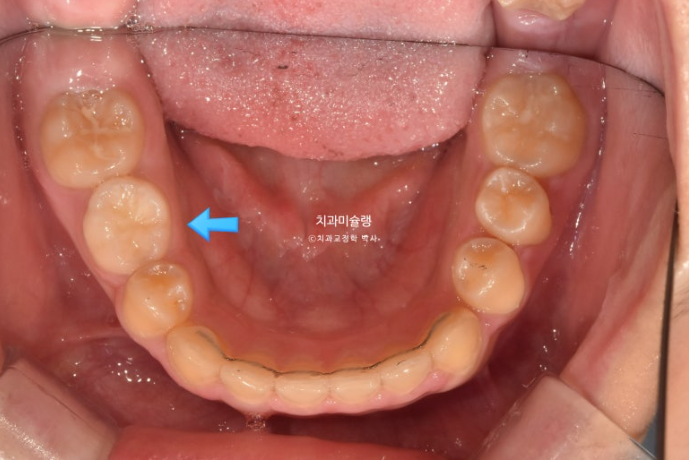

파란화살표 자리에 있어야할 작은어금니가 선천적 결손 상태입니다.

이런 경우 계승영구치가 없어 오래도록 남아있게될 잔존유치를 최대한 보존해서 쓰는 방법으로 치료를 합니다.

잔존유치를 오래 보존해서 사용하기로 했다면 교정 치료 중 불필요한 치아이동에 의해 잔존유치치근이 녹아 짧아지지 않도록 각별히 신경써야 합니다.

유치는 교정력을 받았을때 영구치와 다르게 잘 움직이지 않을 뿐더러, 안그래도 영구치에 비해 뿌리가 약한 상태이니 치근흡수라도 나타나면 발치해야 하는 애매한 상황이 생깁니다.